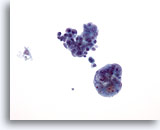

Figure 72

Lymph node FNA, malignant lymphoma.

This specimen is cellular with all cells scattered throughout the photo. Compare a small mature lymphocyte with the vast majority of the rest of the cells that are slightly enlarged. 20x

Lymph node FNA, malignant lymphoma.

This specimen is cellular with all cells scattered throughout the photo. Compare a small mature lymphocyte with the vast majority of the rest of the cells that are slightly enlarged.

20x